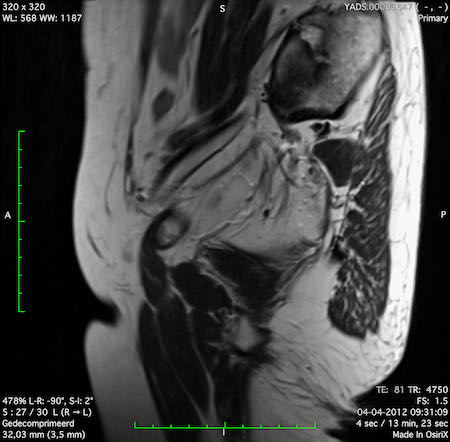

Hình ảnh

Các hình ảnh được cung cấp cho thấy ung thư biểu mô tế bào nhẫn với tình trạng dày lan tỏa thành trực tràng, hình ảnh bia bắn điển hình, và sự xâm lấn mỡ mạc treo trực tràng.